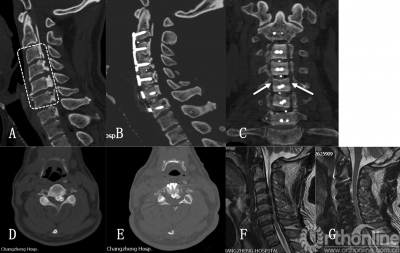

近年来,ACAF成为一种全新的治疗颈椎OPLL的手术方法,该术式通过将椎体骨化物复合体整体前移达到扩大椎管、减压脊髓的目的。孙璟川等人对13例行ACAF手术患者的临床资料进行研究,肯定了ACAF的短期疗效。

手术示意图

病例:59岁男性,多节段OPLL,行C3~C6ACAF手术治疗,患者术后神经系统症状明显缓解,JOA评分从7分提高到15分,改善率80%.

ACAF结合了传统颈椎前路手术直接减压和颈椎后路手术操作安全的特点,有效扩大了颈椎椎管矢状径及椎管横截面积,降低了椎管狭窄率,彻底减压脊髓,短期随访疗效良好,可作为治疗颈椎OPLL的选择方案.